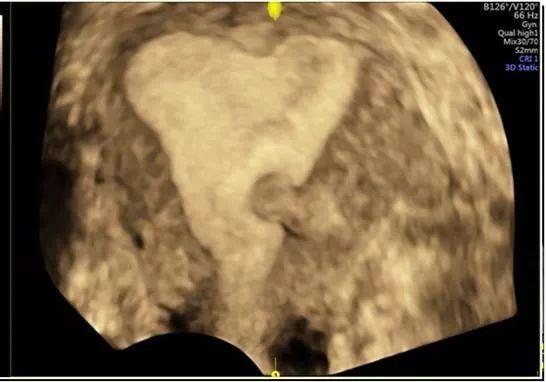

临床上一般根据子宫肌瘤的生长位置分类:

- 肌壁间子宫肌瘤,又称子宫肌层内子宫肌瘤,约占60%-70%;

浆膜下子宫肌瘤,凸向子宫表面,约占20%;

粘膜下子宫肌瘤,凸向子宫内膜,约占10%。 - 子宫肌瘤可能为多发性,也可有上述2个或者3种肌瘤同时存在,又称为多发性子宫肌瘤。